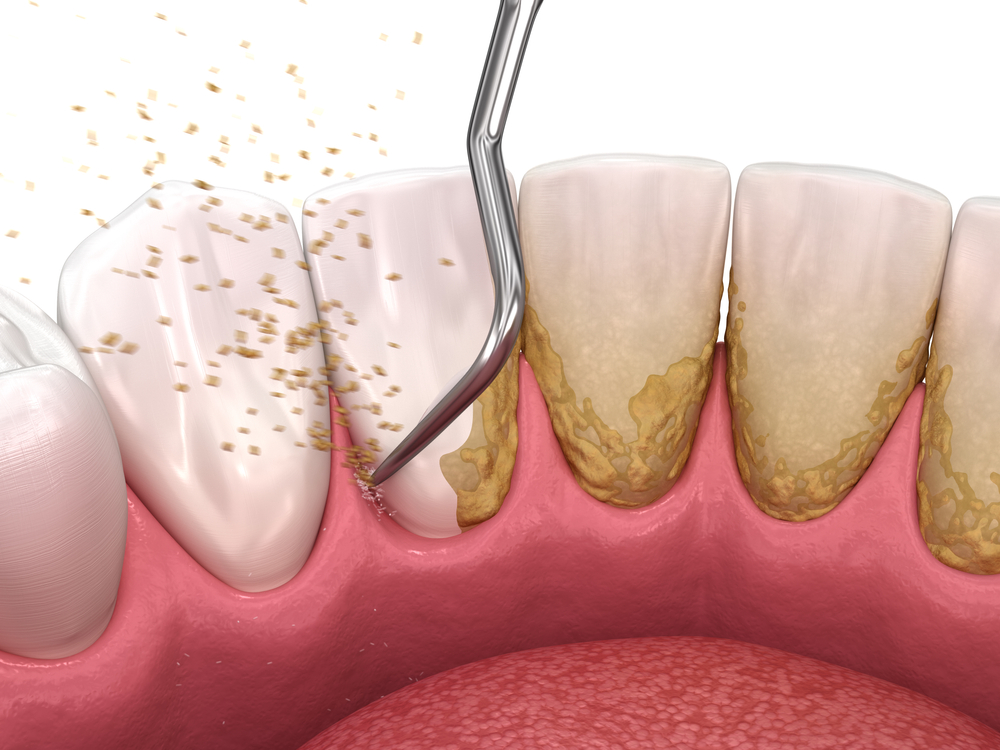

이러한 찌꺼기가 시간이 지나

굳으면 치석이 되어 잇몸에

염증을 일으킬 수 있습니다.

칫솔질만으로는 모든 치면의

이물질을 완벽하게

제거하기 어렵습니다.

특히 어금니 안쪽이나

치아 사이처럼 칫솔이

잘 닿지 않는 부위에는

플라그가 남기 쉬워,

시간이 지나면 단단하게

굳어 치석으로 변합니다.

이 치석은 세균이 번식하기

좋은 환경을 만들고,

결국 잇몸 염증이나 구취,

잇몸 퇴축 등으로

이어질 수 있습니다.

치석이 오래 쌓이면 단순한

세정만으로 제거하기 어려워지고

잇몸이 약해져 치아가

흔들리는 원인이 되기도 합니다.

스케일링은 단순히 치석을

제거하는 데서 그치지 않으며,

치석 제거 과정에서 잇몸

상태를 함께 확인할 수 있어

잇몸 질환을 초기에

발견하는 데도 큰 도움이 됩니다.